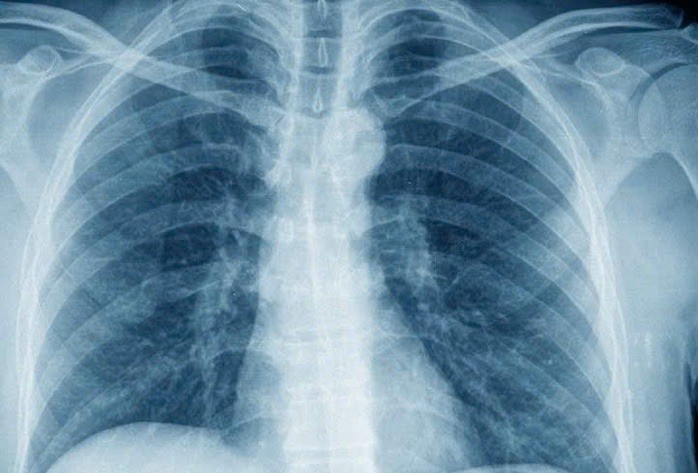

Trước phản ánh về việc chụp X-quang dưới 6 phút không được quỹ BHYT thanh toán, Bộ Y tế cho biết sẽ sớm tháo gỡ, bảo đảm quyền lợi người bệnh (Ảnh: Ngọc Dung)